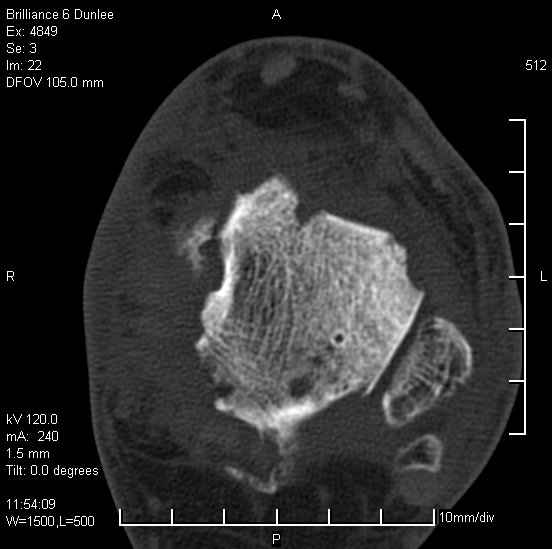

На лечении находится пациент 35 лет. Травма в сентябре 2008 г.- открытый вывих таранной кости

В день травмы ПХО, вправление вывиха, трансартикулярная фиксация. Рана зажила первично. С января нагрузка на конечность. С конца апреля- болевой синдром. На рентгенограммах и КТ признаки ас. некроза таранной кости, артроз подтаранного и голеностопного суставов.

У больного тотальный ас. некрох блока таранной кости, заинтересованы голеностопный и подтараный суставы. Эндопротезирование маловероятно на некротизированную кость. Изолированный подтаранный артродез таран не спасет.При артродезе всю некротизированную кость придется убрать.А далее замещение либо за счет большеберцовой кости, или удлинение на регенерате.